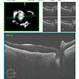

- full thickness macular hole

Scanning laser ophthalmoscope

- A 32 years old female presents with complains of diminution of vision in right eye with Full thickness retinal hole involving the fovea.